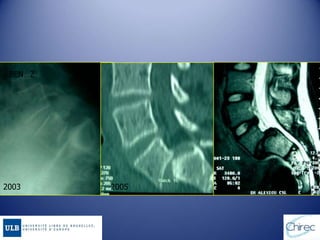

BEN…Z

2003 2005

Evolution du glissement

HISTOIRE NATURELLE Rupture ouallongement isthmique du petit enfant sous l’effet de facteurs favorisants (dysplasiques +++) Glissement rapide Formes à grand déplacement Haut grade Formes à sacrum horizontal Bon pronostic Formes à sacrum vertical Mauvais pronostic J.L Jouve